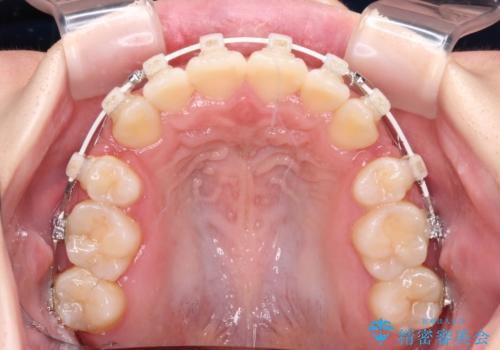

上下非接触で突出した前歯 ワイヤー装置による抜歯矯正

- 矯正装置

- 審美装置

- 上下前歯の隙間と口元の出っ張った感じを気にして来院された患者様です。

上下の隙間は舌突出癖によるもので、またその癖により前歯が前方に出ている状態でした。

口元の出っ張りを改善するため、上下左右第一小臼歯4本を抜去し、ワイヤー装置にて矯正治療を行うこととしました。

舌の突出癖を改善するためのトレーニングをしっかりと行っていただいたことで、比較的スムーズに治療を進めることができました。

口元の突出感もしっかりと改善することができました。